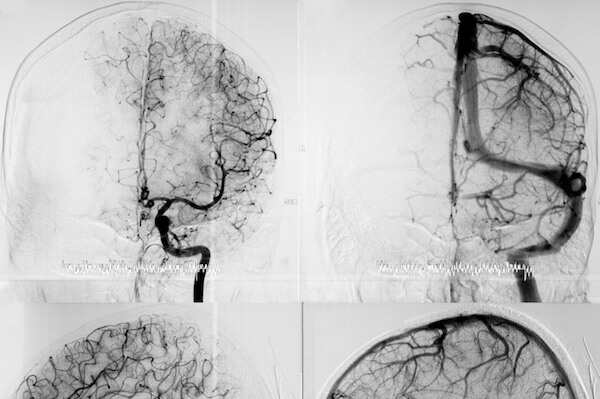

- embolizzazione di aneurismi cerebrali attraverso la tecnica del coiling o l’impianto di flow diverter

- embolizzazione di MAV (malformazioni arterovenose), FAV (fistole arterovenose) o FAVD (fistole arterovenose durali, ovvero fistole localizzate nello spessore durale)